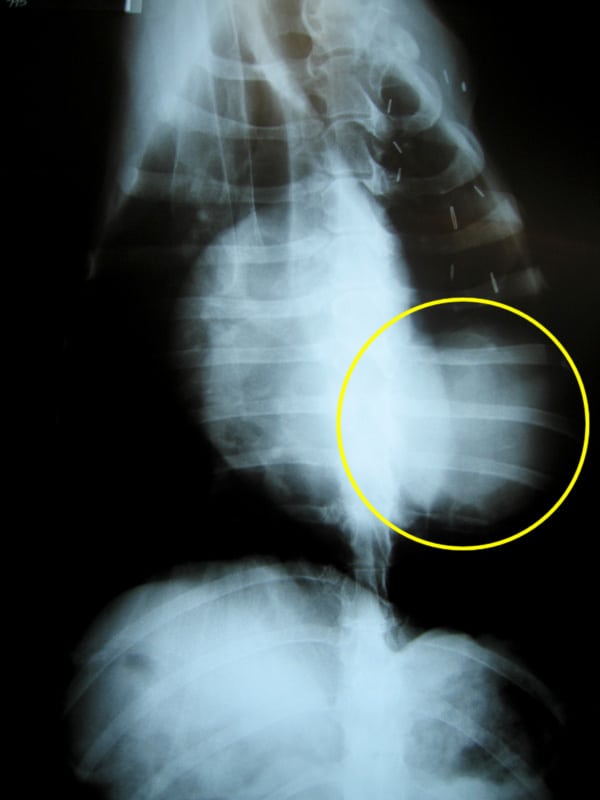

Tomorrow we’ll get the results from tests on blood and urine samples they took from me. But the films clearly indicate that I do indeed have a lump in my lung. More of a mass really, about the size of a softball from the looks of things. But as I have proven all along, I’m a special case.

osteosarcoma metastasis xrayUsually, osteosarcoma metastasis presents itself as multiple legions throughout the lungs. The doctor expected to see a “snowstorm” on the x-rays. And I could tell my people did too, deep down inside. Instead, I appear to have a single large growth, which may or may not be operable.

In fact, it may or may not have anything to do with my cancer at all. That’s probably not the case, but the doctor did mention the rare possibility that it could be totally unrelated. Perhaps he was just trying to keep our hopes up.